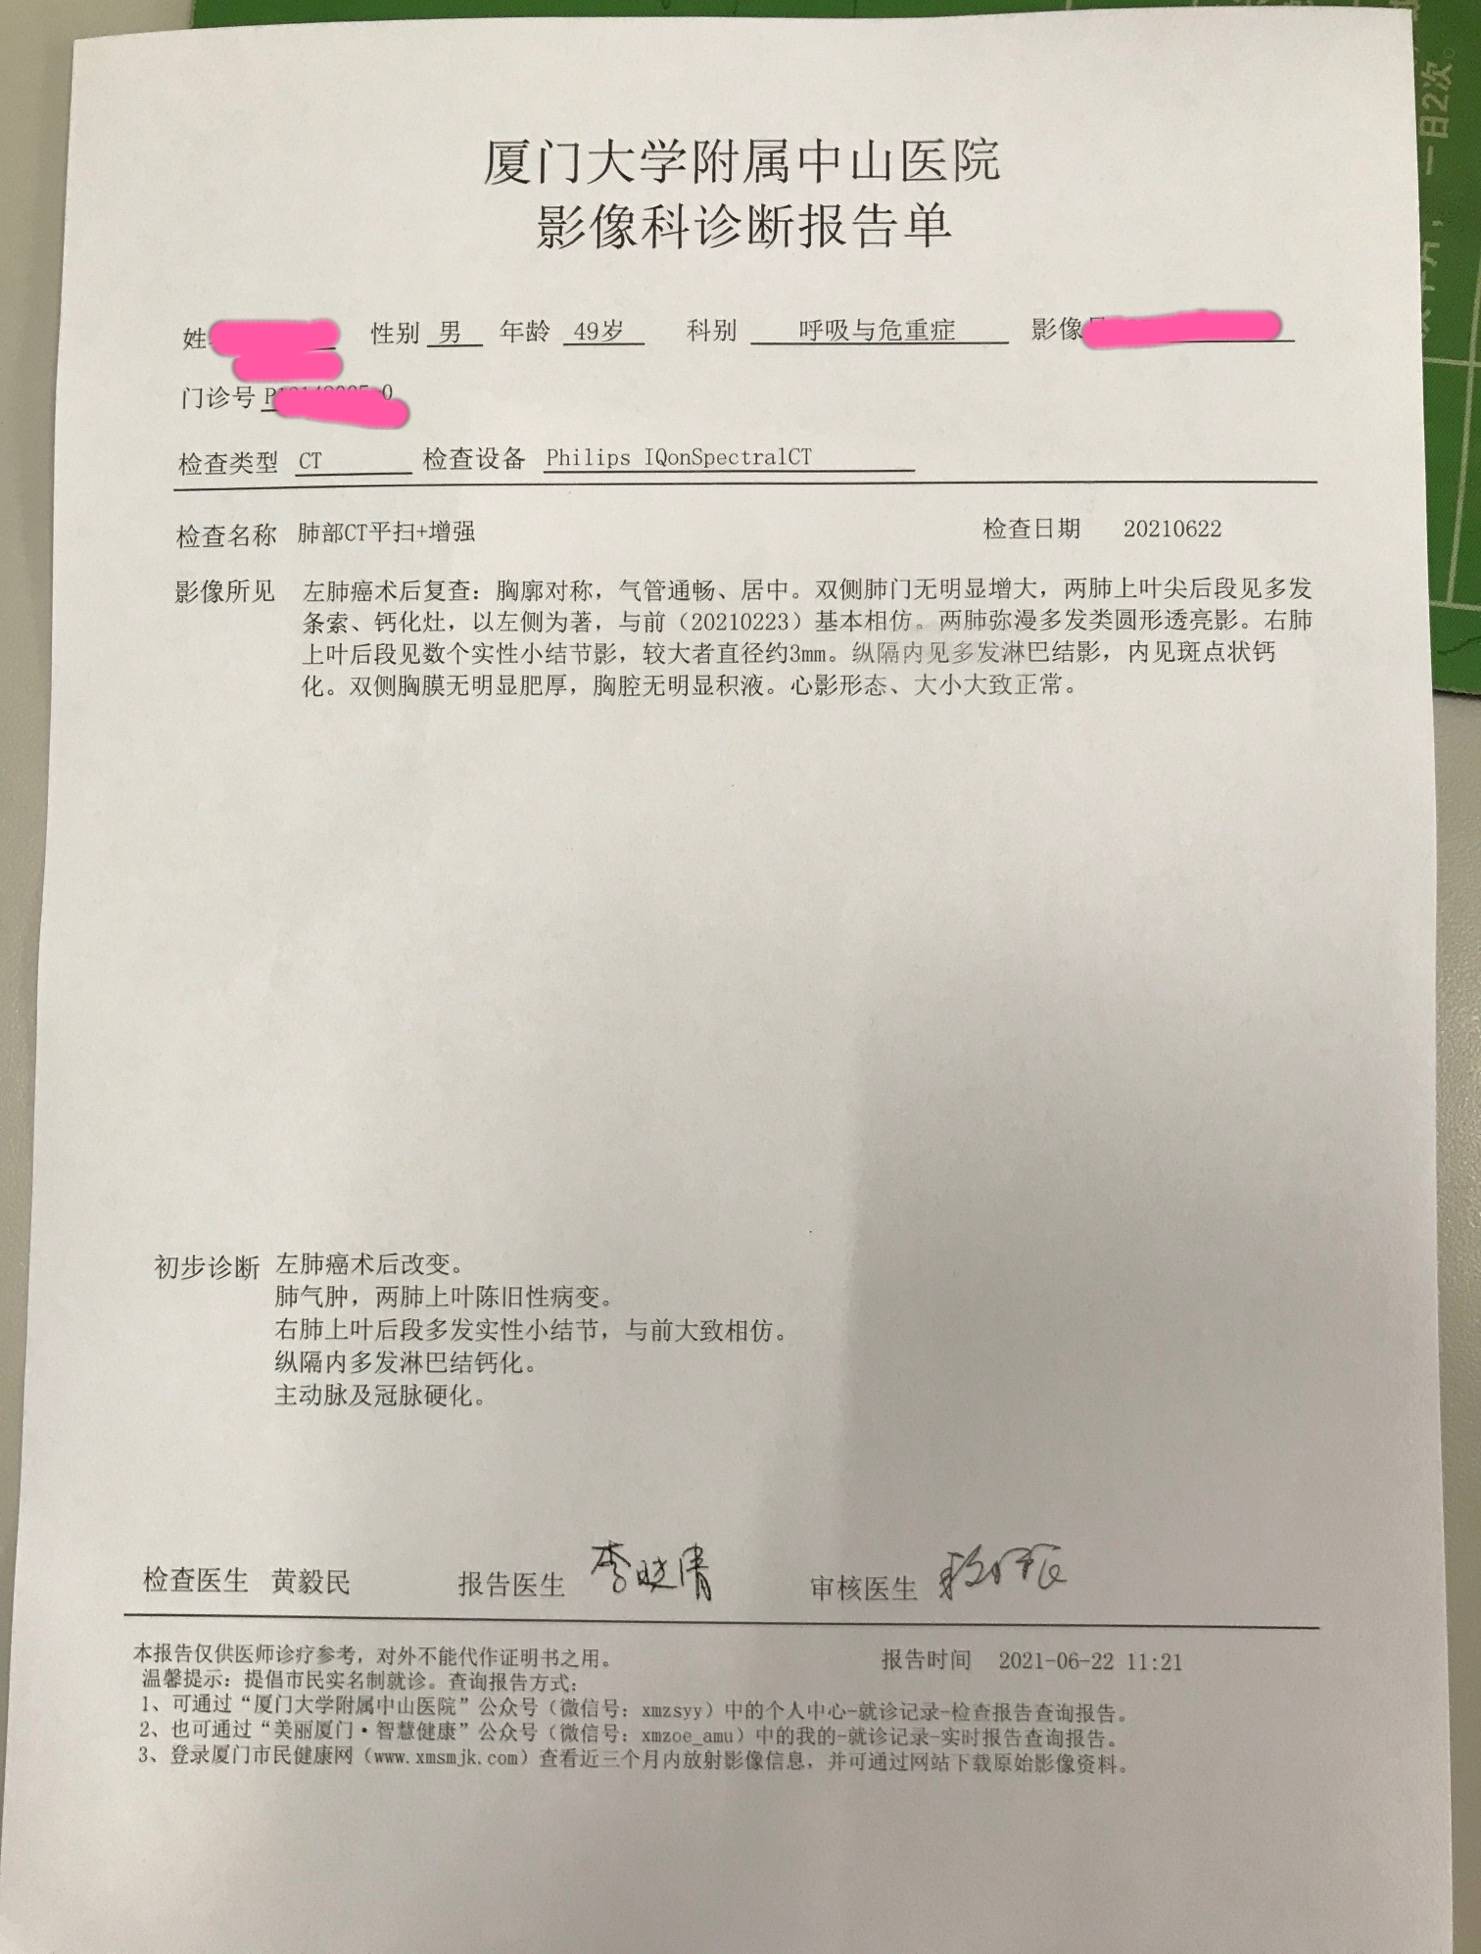

等待手术的过程中,患者怕淋巴结区域继续进展,就在另一家医院就近又复查了CT

结果出来惊得患者目瞪口呆

报告竟然报术后改变

患者没有做手术呀!

患者很惊讶!莫非拿错报告了?发生了左腿切右腿,男性报告有卵巢这种荒谬的事情

经过陈某某核对,图像确实是患者的